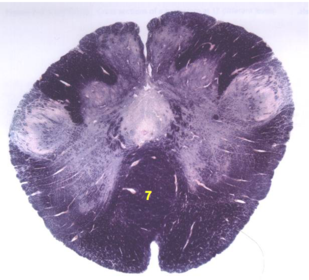

| Nucleus gracilis | |

| Nucleus cuneatus | |

| Fasciculus gracilis | |

| Fasciculus cuneatus | |

| Internal acruate fibers | |

| Lateral (external/accessory) cuneate nucleus | |

| Medullary pyramids | |

| Hypoglossal nucleus | |

| Hypoglossal nerve | |

| Dorsal motor nucleus of X | |

| Nucleus ambiguus | |

| Solitary tract | |

| Solitary nucleus | |

| ALS | |

| Medial lemniscus | |

| Medial longitudinal fasciculus | |

| Spinal tract of V | |

| Spinal nucleus of V | |

| Lateral (external, accessory) cuneate nucleus | |